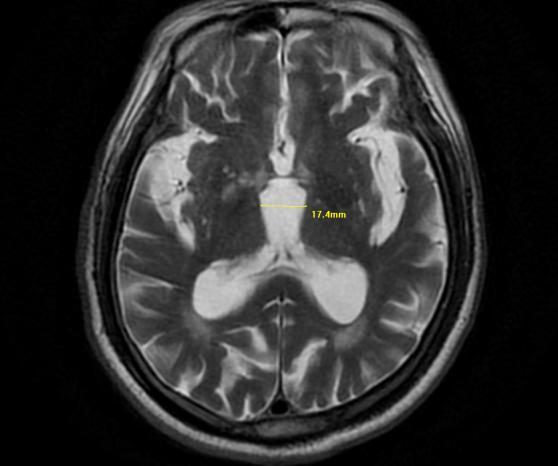

为了证实推断,医生调取了王大爷的脑部核磁共振图像。在脑干中脑部位的矢状位图像上,一个典型的特征出现了,熊猫体育官方中脑组织明显萎缩,侧面轮廓看起来就像一只蜂鸟的剪影。

它并非真的有一只鸟,而是中脑萎缩后,在影像上形成的特殊形态。正是这只“蜂鸟”,揭示了困扰老人三年的病根。